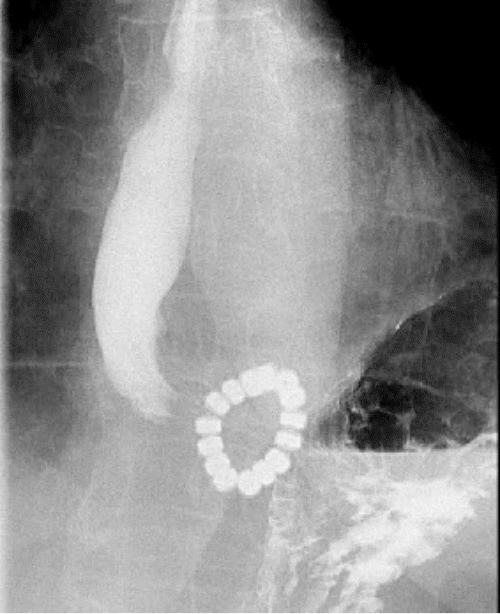

The patient was referred to our institution for a second opinion on her dysphagia five years after device implantation. At her presentation, she reported difficulty swallowing with all food consistencies. We performed a comprehensive workup to investigate the etiology. Barium esophagram revealed delayed esophageal emptying and a concerning finding—dissociation of the posterior beads of the LINX system (Figure 1). This dissociation was not documented on prior studies, although image comparison was limited due to unavailability. High-resolution manometry (HRM) demonstrated persistent issues despite a previous repair attempt. Despite 100% bolus clearance, the test showed weak esophageal peristalsis and a recurrent 2 cm hiatal hernia. There was no device erosion or malposition on EGD.

Figure 1. Barium Esophagram. Published with Permission

A.

Illustrating discontinuity in the posterior section of the LINX device during contrast passage. A) Pre-contrast image shows the LINX device in its intact state

B.

Illustrating discontinuity in the posterior section of the LINX device during contrast passage.  B) Following contrast passage through the device, separation is evident between the posterior beads (indicated by arrow).